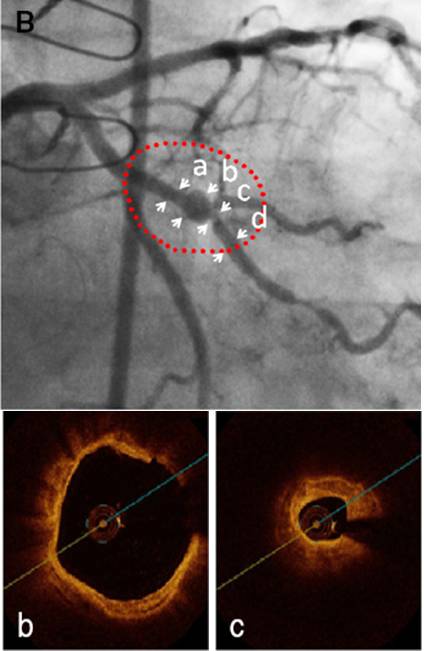

冠心病?

◆无冠心病危险因素,冠状动脉 CTA 正常,可排除

◆IgG4 相关的心血管疾病:累及胸主动脉、腹主动脉、冠状动脉及一些小动脉,形成动脉瘤、假瘤、心包炎

◆本例患者心脏扩大、CLBBB,不能用冠状动脉病变解释

◆先后出现浸润性眼病、胆管炎,后出现心脏扩大、EF进行性下降,常规抗心室重构药物治疗无效,提示为系统性疾病的心脏表现